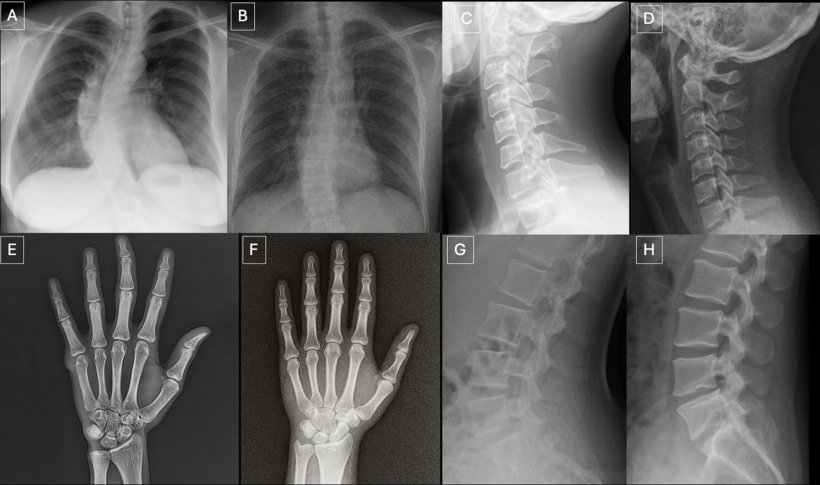

Real or fake? AI-generated X-rays have become suprisingly convincing (Quiz yourself!)

Deepfake medical images often look too perfect. Bones are overly smooth, spines unnaturally straight, lungs overly symmetrical, blood vessel patterns excessively uniform, and fractures appear unusually clean and consistent, often limited to one side of the bone

Seventeen radiologists from 12 different centers in six countries (United States, France, Germany, Turkey, United Kingdom and United Arab Emirates) participated in the retrospective study. Their professional experience ranged from 0 to 40 years. Half of the 264 X-ray images in the study were authentic, and the other half were generated by AI. Radiologists were evaluated on two distinct image sets, with no overlapping between the datasets. The first dataset included real and ChatGPT-generated images of multiple anatomical regions. The second dataset included chest X-ray images—half authentic and the other half created by RoentGen, an open-source generative AI diffusion model developed by Stanford Medicine researchers.

The study identified common features of synthetic X-rays. "Deepfake medical images often look too perfect,” Dr. Tordjman said. “Bones are overly smooth, spines unnaturally straight, lungs overly symmetrical, blood vessel patterns excessively uniform, and fractures appear unusually clean and consistent, often limited to one side of the bone."